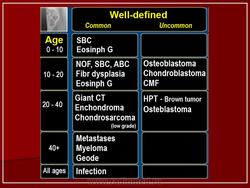

Дифференциальная диагностика изображения